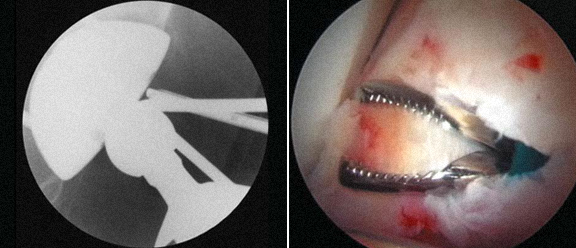

3 - Corpos livres visíveis nas imagens de Rx e TAC, e extração por artroscopia